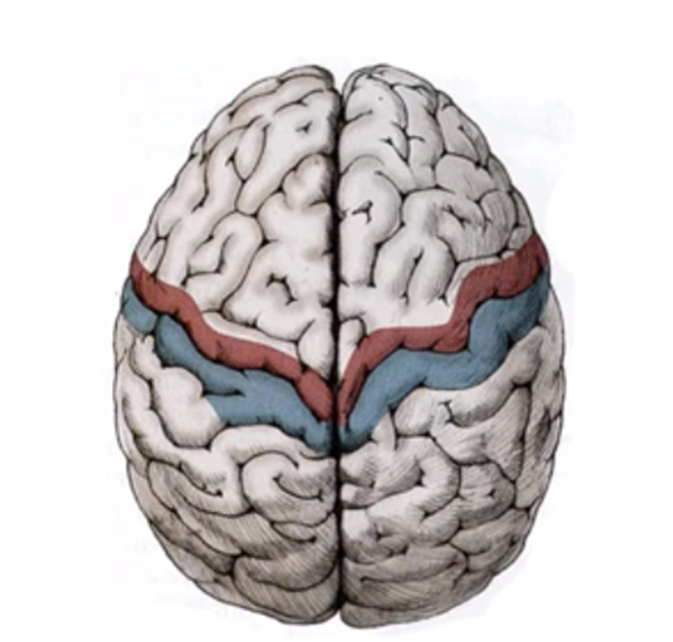

.在大腦的模型中, 我們可以看見藍色部分為體感皮質(somatosensory cortex), 而紅色部分為運動皮質(motor cortex), 運動皮質(motor cortex)控制我們的活動, 兩組皮質互相緊密合作去控制我們的身體